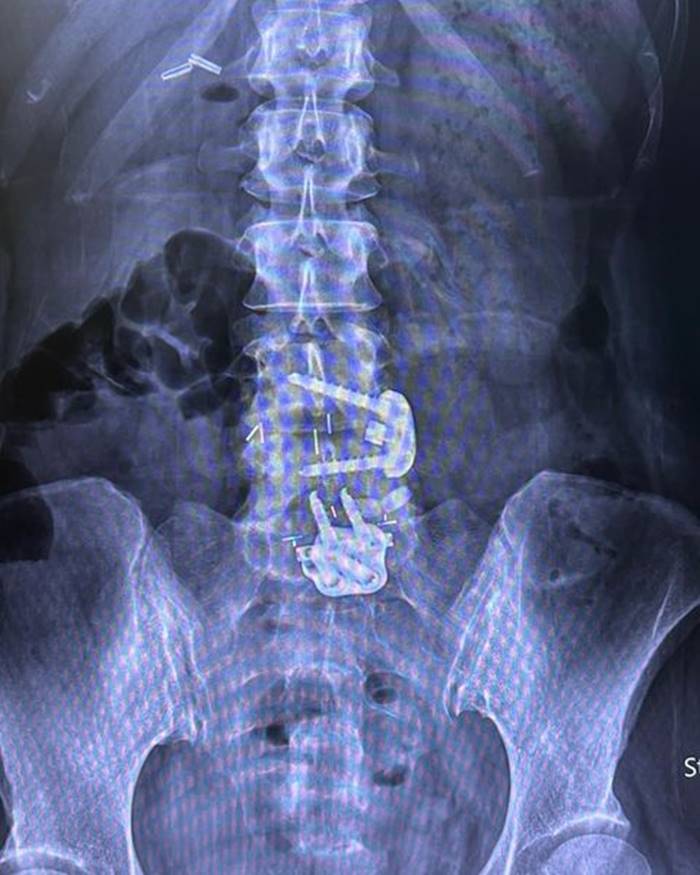

อยากขอเตือนเพื่อนๆ นะคะ ว่าถ้าออกกำลังท่าไหนแล้วรู้ตัวว่าไม่ไหวก็ให้บอก trainer ค่ะ อย่าฝืนทำ เพราะลงท้ายอาจจะต้องผ่าตัดแบบหนุ่ย.. trainer ให้ทำ Squat ที่หนุ่ยก็หันไปบอกแล้วว่าหนักไปทำไม่ได้ เค้าก็ยังให้ทำ ผลคือหมอนรองกระดูกปลิ้น ต้องผ่าตัดใส่เหล็กตามภาพเลยค่ะ..ตอนนี้ก็ต้อง slowlife ไป 4-5 เดือน”